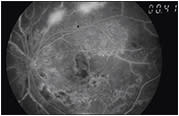

FFA is also important in cases of very poor BCVA with featureless retina, which can indicate ischemic maculopathy and is a sign of poor prognosis that can be distinguished on FFA as enlargement of the foveal avascular zone (FAZ) or as a FAZ with irregular borders (Figure 4).

Figure 4. Diabetic macular ischemia with enlarged foveal avascular zone, telangiectasia, and capillary dropout with neovascularization; this patient has BCVA of counting fingers.